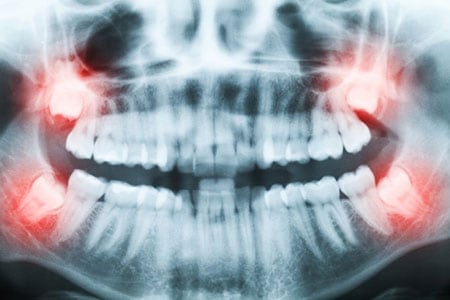

Why do wisdom teeth need to be removed?

Wisdom teeth are your far-back molars that are the last teeth to grow in. Many become “impacted” due to overcrowding in your mouth. Impacted wisdom teeth can be a source of significant discomfort and are an area where bacteria accumulation and infection are more likely. Our dentists recommend extracting wisdom teeth that pose these problems.